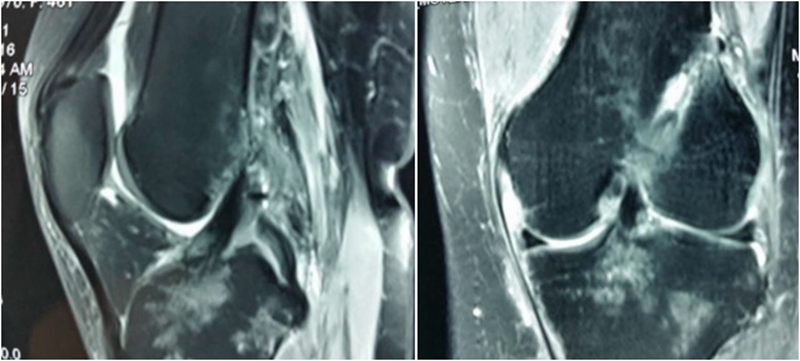

典型病例,张X,男,18岁,因扭伤致左膝关节疼痛伴活动受限1月余入院。

诊断:1.左膝前交叉韧带损伤;2.左膝外侧半月板损伤合并囊肿。

术前MRI

术后MRI